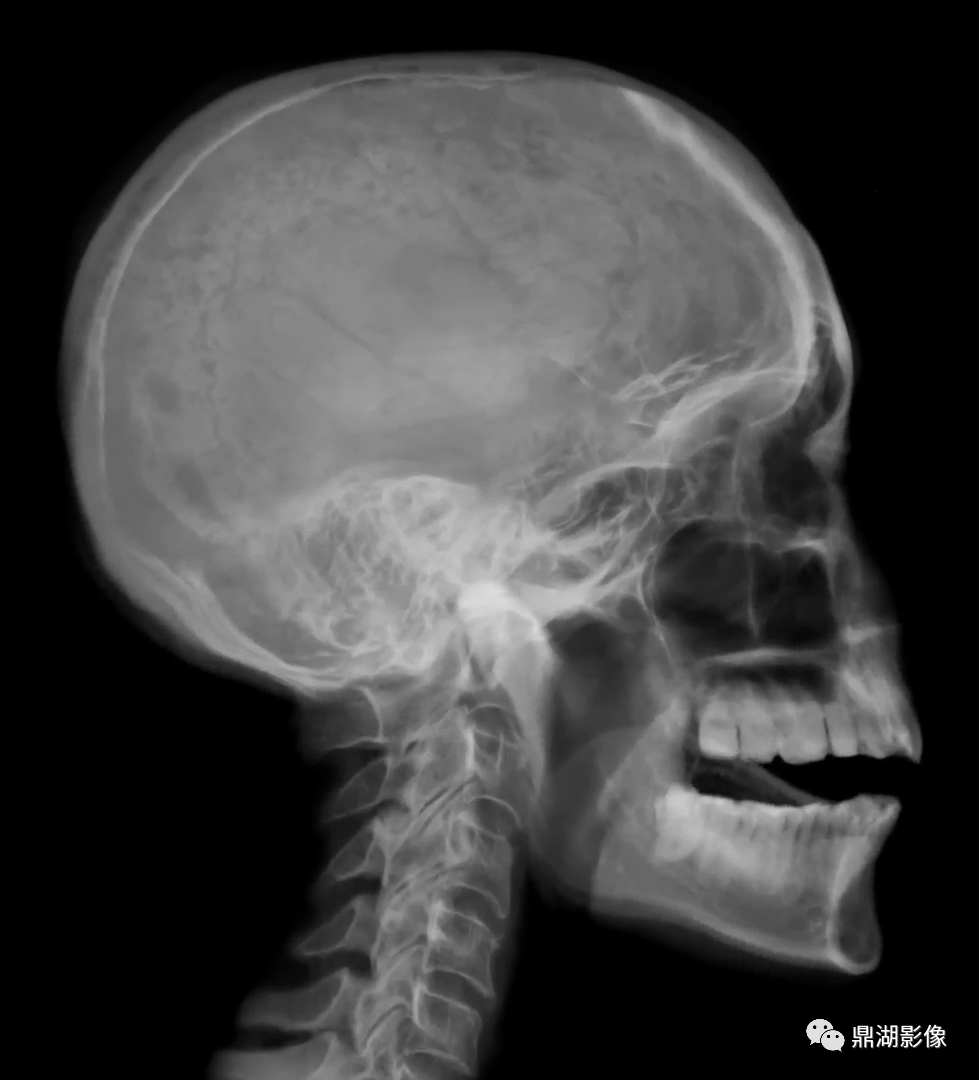

正常颅骨X光片

1.头颅大小与形状

头颅大小与形状做一般观察即可,如生长发育时期,头颅大小变化较大,形状个体差别也较大。

2.颅骨厚度、密度、结构

生长发育时期,颅骨厚度、密度、结构变化较大,新生儿的颅壁薄而光滑,6岁以前颅壁分不出内外板与板障,厚度与密度也均较小。

3.颅缝与囟门

颅盖骨在膜性基质上生出多个化骨核,在化骨核之间,以结缔组织相隔,较细者称为“缝”,较大者称为“囟”。新生儿头颅有6个囟,居顶骨四角,即前囟、后囟或枕囟、前外侧囟或蝶囟后外侧囟或乳突囟。此外还可有副囟位于矢状中线,如眉间囟、额囟和小脑囟等。脑膜膨出或脑膜脑膨出易由副囟处膨出。囟在X线上表现为边缘较清楚的不规则多角形透明区。

颅缝在颅盖骨可见冠状缝、矢状缝、人字缝,X线上为线状或带状透明影像。

颅缝和囟随年龄增长而逐渐闭合变窄,封合速度因人而异。双侧对称的缝,封合速度可有不同。

五、颅底

颅骨侧位上,前、中、后颅凹底从前向后依次低出三下,呈阶梯状。

四、蝶鞍

蝶鞍位于颅底中央,前以鞍结节,后早以鞍背为界。侧位显示清楚。

1.大小:蝶鞍前后径平均为11.7mm,确定蝶鞍增大,不能只依靠测量结果。

2.结构:蝶鞍在小儿松质骨较多,皮质不似成人分那样形成良好,所以密度较低,边缘不清。鞍背常较厚、较短,边缘不清,且较直立。鞍结节与后床突较小或不显。蝶枕联合经常可以看到,成人骨质密度较大,皮质清楚,床突与鞍结节较大,蝶鞍后壁边缘清楚。